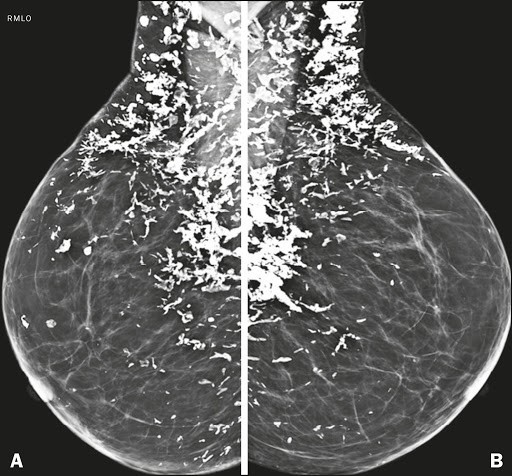

dermal calcs:

most common in the parasternal area and inframammary fold